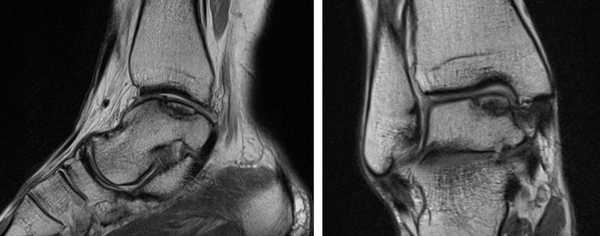

МРТ является ценным инструментом в комплексе диагностики ОХПТК для оценки отека костной ткани, а также выявления скрытых повреждений субхондральной кости и хрящевого покрытия, которые могут быть пропущены при стандартных рентгенограммах или даже КТ. МРТ - самый лучший инструмент оценки для определения стабильности и жизнеспособности фрагмента таранной кости при его отслоении и эта информация может быть решающей в тактике выбора того или иного метода хирургического лечения. Однако, для определения размеров отслоившегося фрагмента таранной кости наилучший метод КТ, так как данные размеров по МРТ могут не соответствовать действительности в сторону переоценки последних. Hepple с соавторами изучив многочисленные данные МРТ диагностики разработали систему классификации ОХПТК на основе этого метода (Табл. 2) [23]. Однако, наиболее широко принятая система классификации, основанная на КТ-это классификация Ferkel и Sgalione (Табл. 3; Рисунок 4) [24]. Классифицировать ОХПТК также возможно выполнить интраоперационно, на основе артроскопических данных о состоянии остеохондрального поражения. Наиболее широко используется система Ferkel/Cheng (Табл. 4) [25], эта система классификации, в отличие от обычных рентгенограмм, КТ и МРТ, лучше всего взаимосвязана с исходами лечения пациентов.

а. схематическое изображение рассекающего остеохондрита таранной кости. б. на МРТ и рентгенограммах определяется рассекающий остеохондрит.

На МРТ выявляется рассекающий остеохондрит с отделением костно-хрящевого фрагмента от таранной кости.